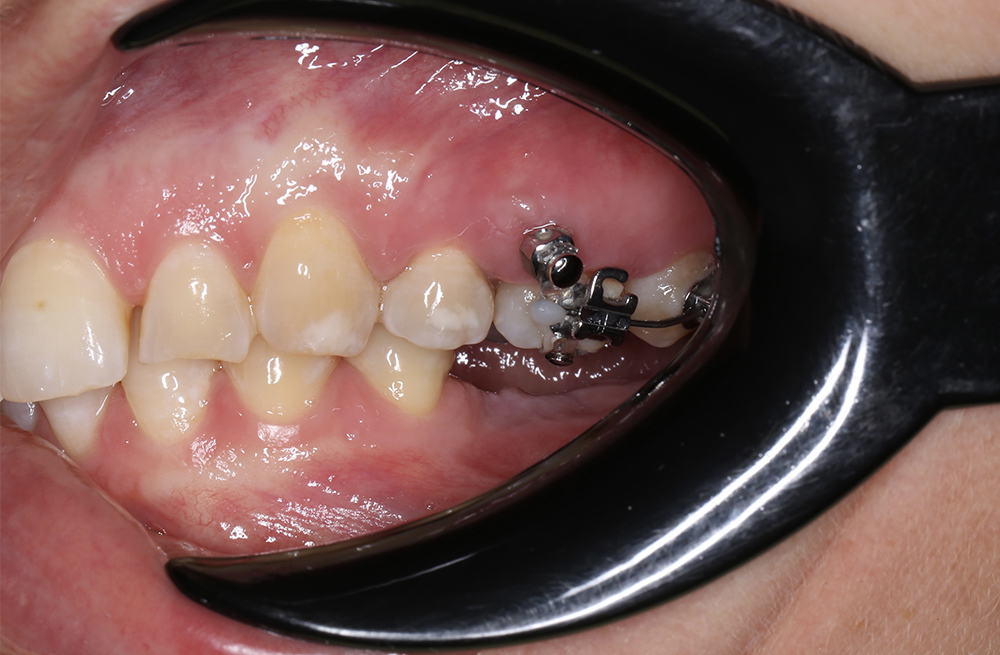

Подготовка места для импланта через устранение смещения зубов с помощью брекетов на минивинтах